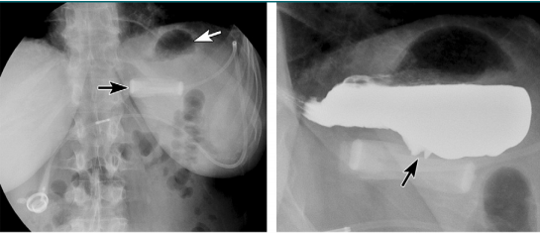

sma syndrome

straight arrow = abrupt cut off of the 3rd portion of the duodenum

curved arrow = incidental duodenal diverticulum